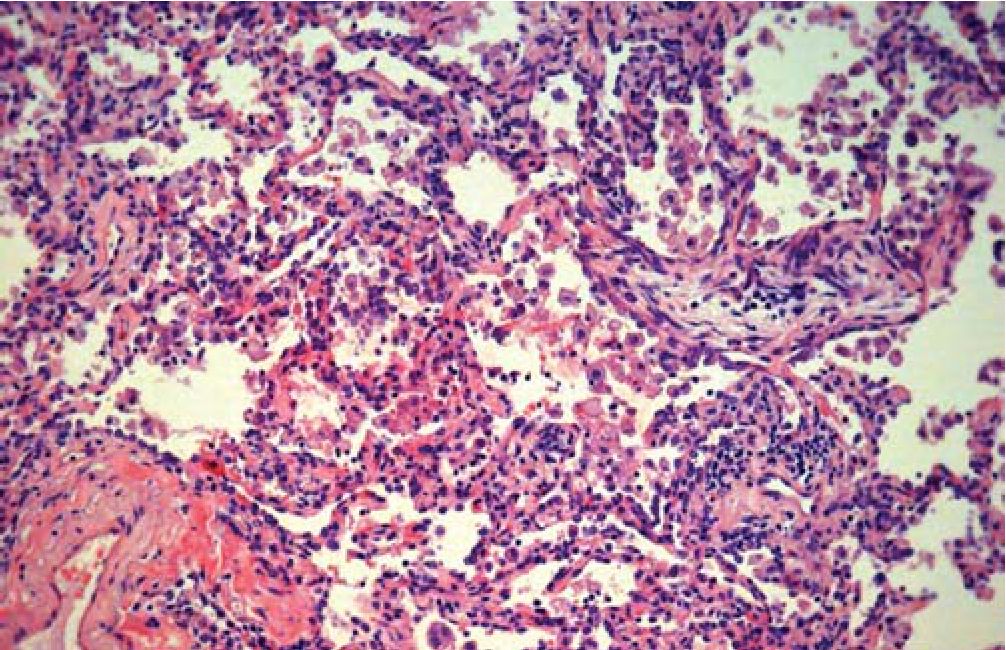

Рис. 2. Грануляционная ткань в просвете респираторной бронхиолы и альвеолярном ходе.

Окраска гематоксилином и эозином. X 40

Ткань легкого деформирована за счет врастания в полости альвеол и просветы части респираторных бронхиол 1-го порядка грануляционной ткани в виде полипов (рис. 2), в части полостей альвеол - скопления макрофагов с примесью эозинофилов (рис. 3) и эритроцитов с единичными эозинофилами, в других просветах альвеол - скопление фибрина с примесью эозинофилов и нейтрофилов, отдельные стенки альвеол несколько утолщена за счет небольшой лимфоцитарной инфильтрации и пролиферации альвеолоцитов 2-го типа. Фиброэластоз стенок мелких ветвей легочной артерии с сужением просветов (рис. 4).